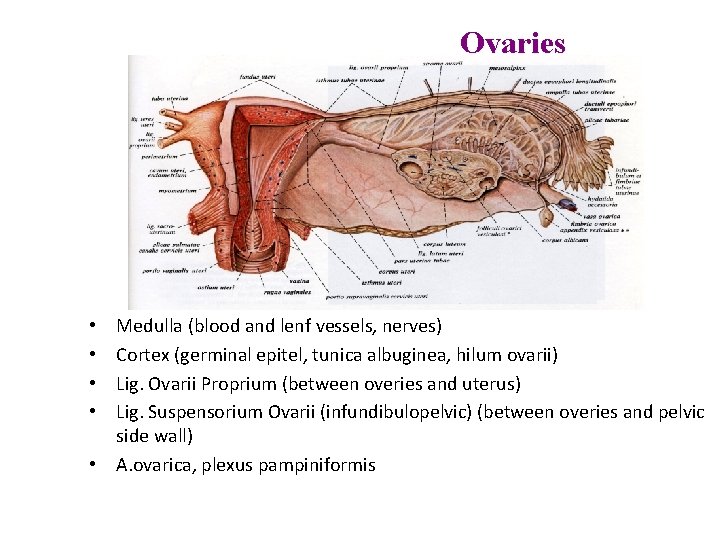

Ovaries Medulla (blood and lenf vessels, nerves) Cortex (germinal epitel, tunica albuginea, hilum ovarii) Lig. Ovarii Proprium (between overies and uterus) Lig. Suspensorium Ovarii (infundibulopelvic) (between overies and pelvic side wall) • A. ovarica, plexus pampiniformis • •